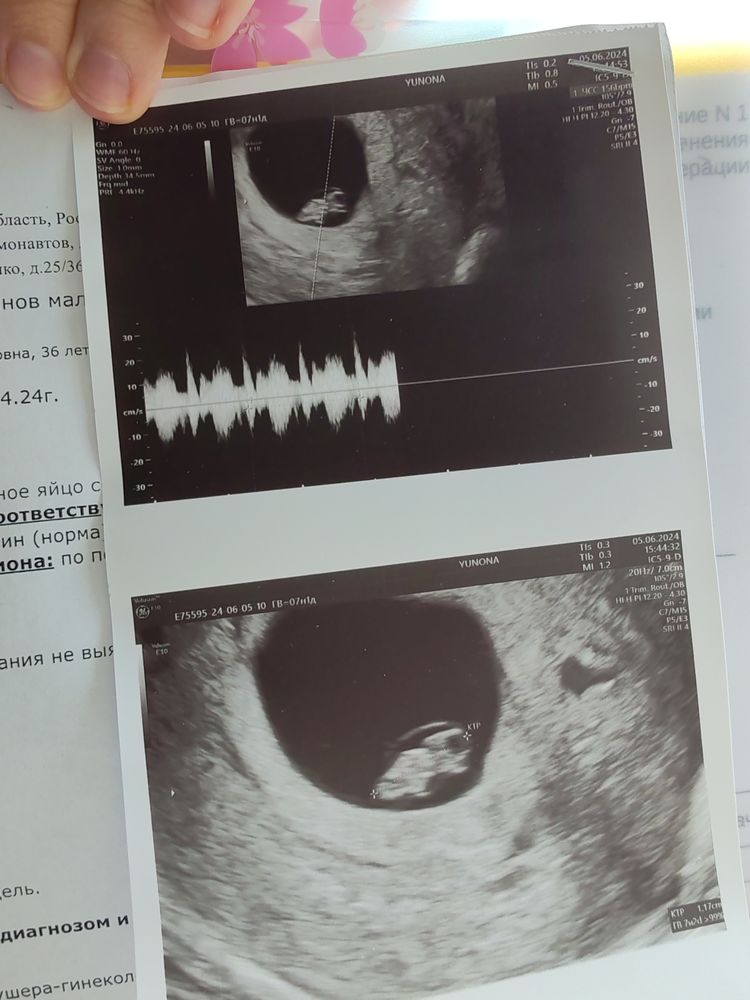

Можно и мне узнать кто будет 6-7 недель

05.01.2021